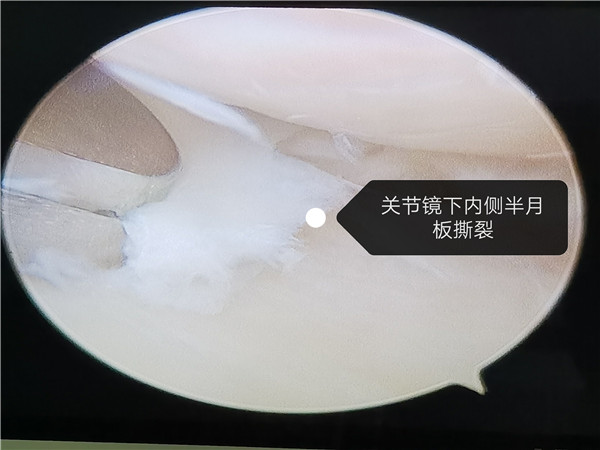

近日,骨一科为一位左膝关节反复疼痛的患者朱先生关节镜下行左膝内侧半月板后角撕裂成型术。据了解,朱先生膝关节一年来反复疼痛不适,多次就诊其他医院,并行多次针灸、敷草药等治疗,症状当时有好转,但很快又会出现疼痛,一个月前症状突然加重,影响行走活动,上下楼梯非常困难,再次行中医治疗,并口服消炎镇痛药,无任何效果。朱先生于6月21日就诊于市三院骨一科进行进一步治疗,刘华凯副主任医师完善相关检查,考虑半月板损伤可能性极大,行左膝关节MRI后提示:左膝内侧半月板后角撕裂。在与患者沟通后,刘华凯为该患者在关节镜下行左膝内侧半月板后角撕裂成型术,术后第二天便能下地行走,疼痛明显缓解,术后三天顺利出院,良好的治疗效果受到了患者和家属的一致好评。

刘华凯副主任医师表示,对于早中期的膝关节疾病患者,关节镜治疗可以明显改善膝关节相关症状,减轻患者的痛苦,皮肤疤痕小,出血少,关节功能恢复快,住院时间短,患者恢复更快。